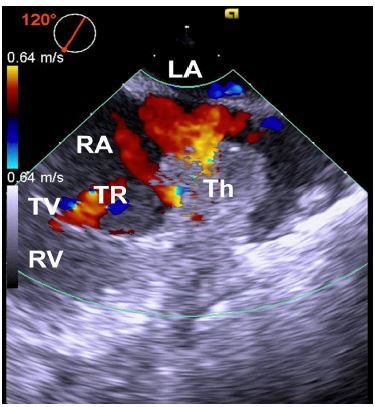

Figure 3: Midesophageal modified bicaval view of transesophageal echocardiography image at 120° with color flow Doppler showing the right atrial portion of the clot and moderate tricuspid regurgitation. LA: Left Atrium; RA: Right Atrium; RV: Right Ventricle; Th: Thrombus; TR: Tricuspid Regurgitation; TV: Tricuspid Valve.